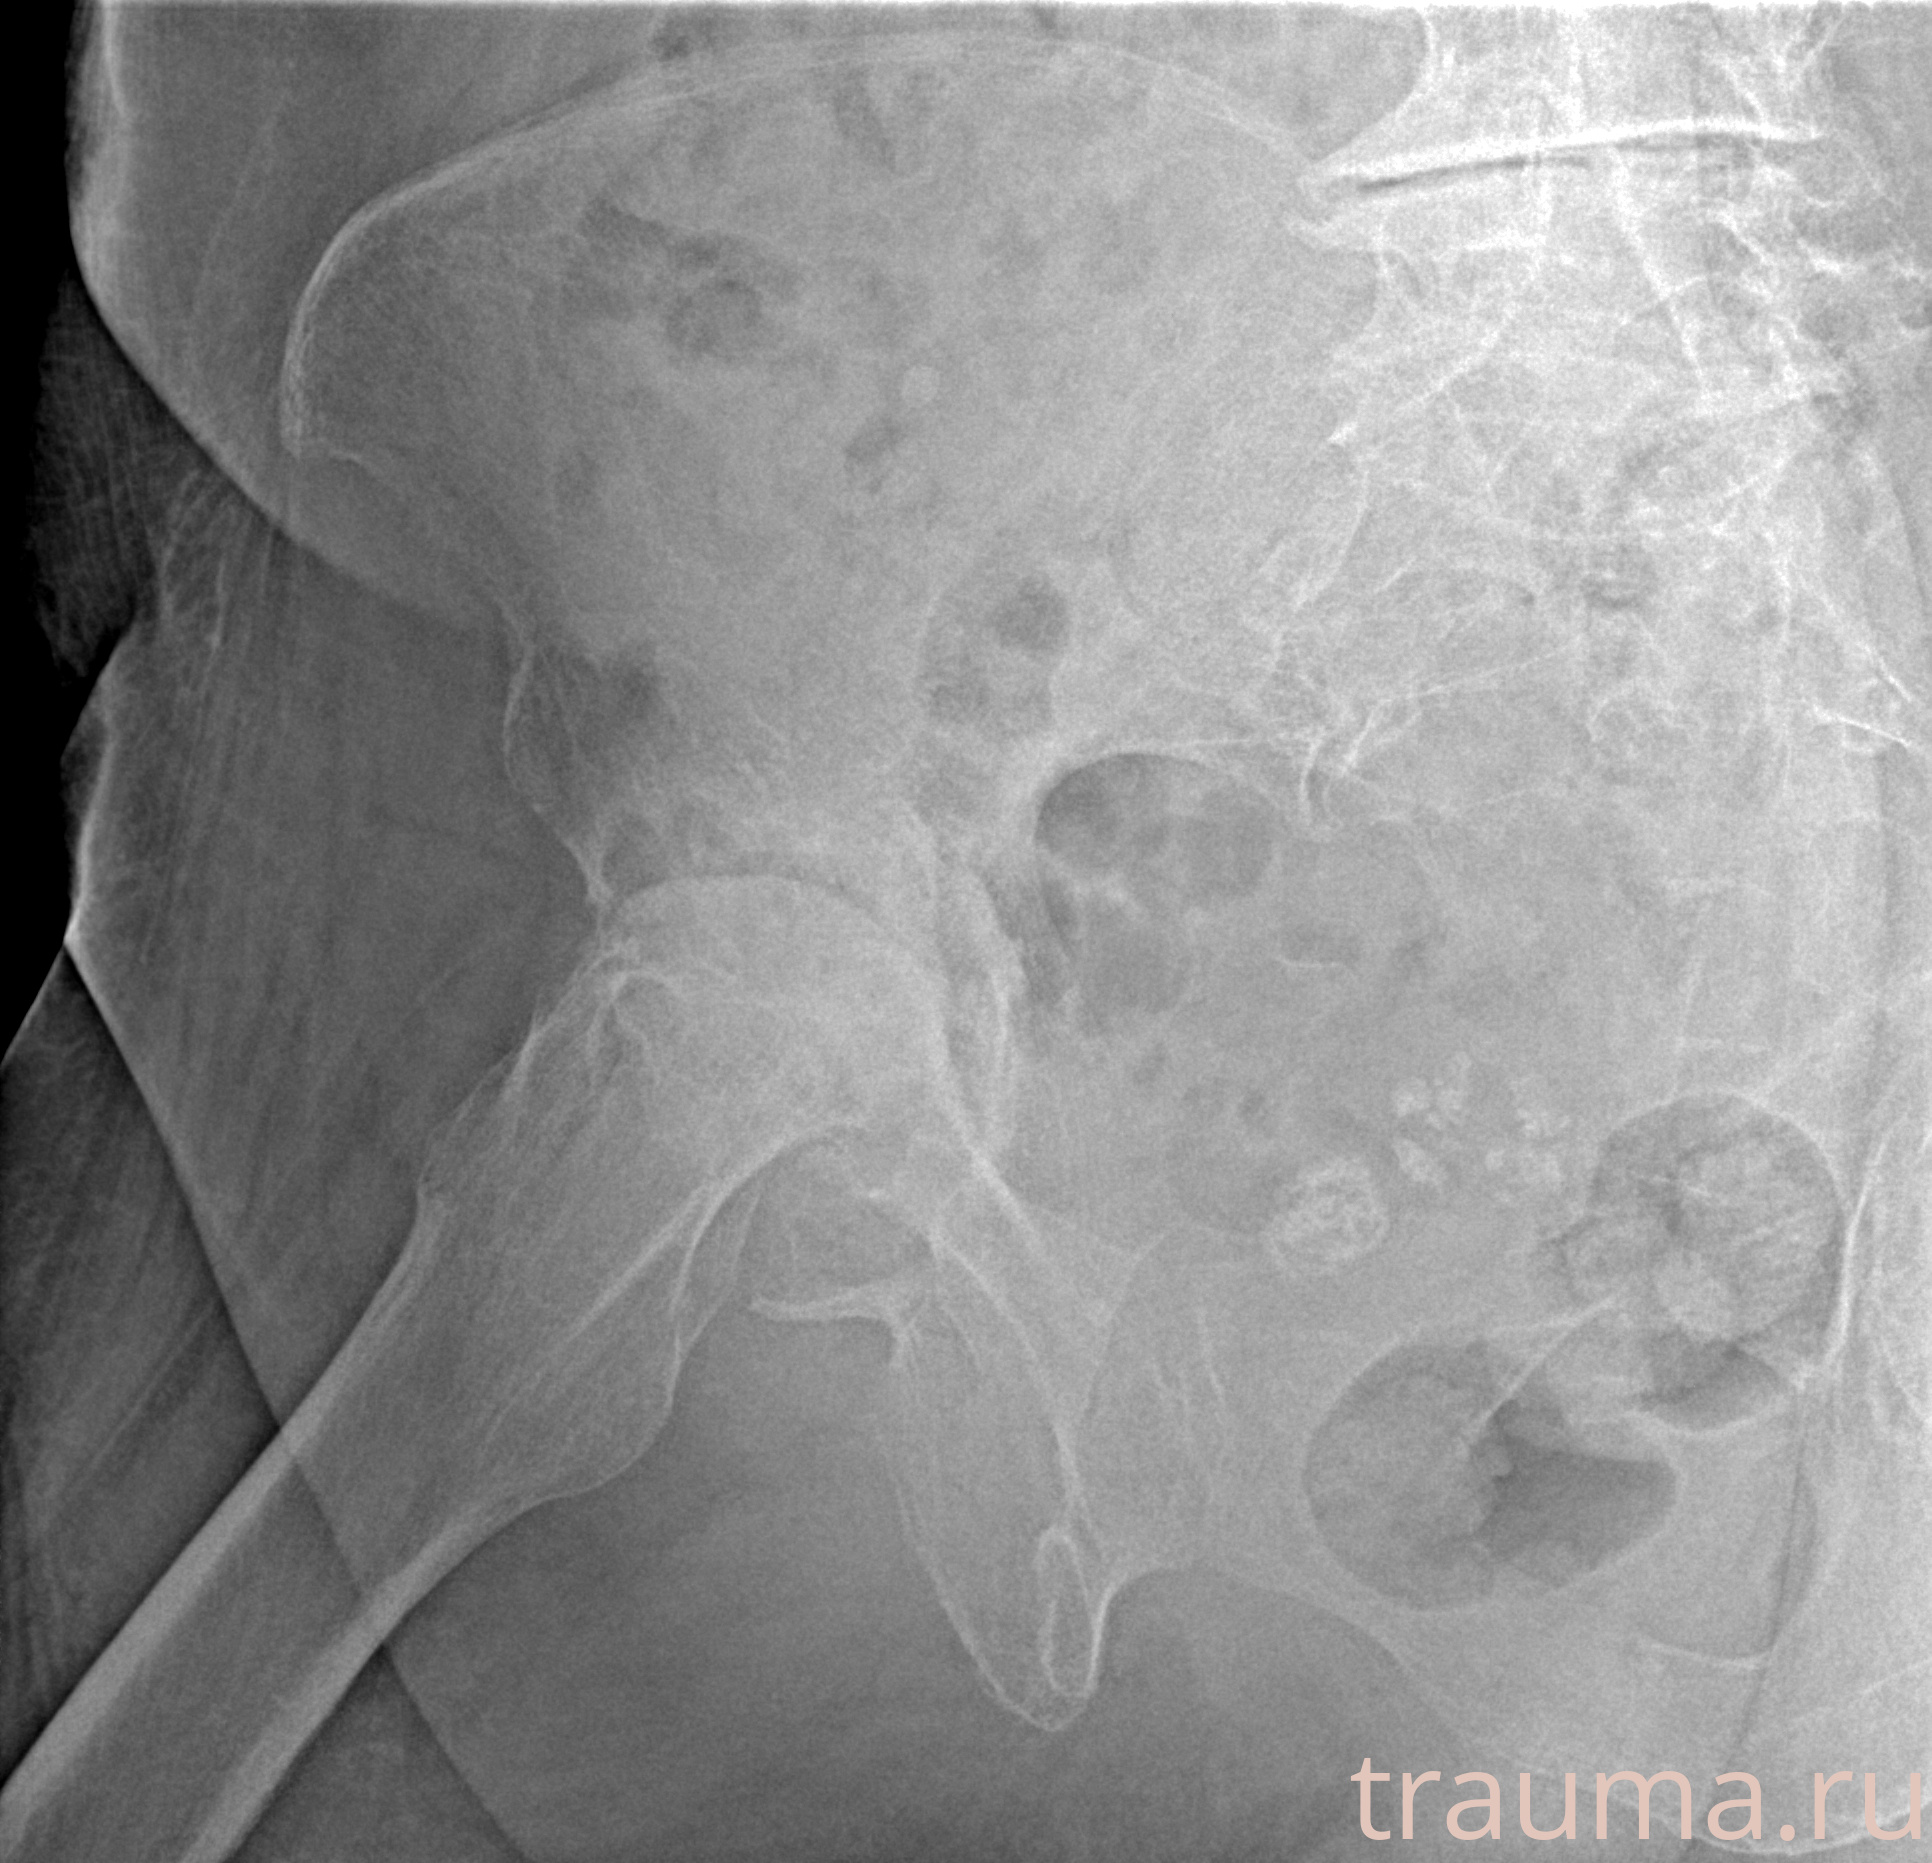

Рентген на дому: по вашему адресу приезжает врач-рентгенолог, травматолог-ортопед с мобильным рентгеновским аппаратом, проводит диагностику травмы или заболевания, делает необходимые рентгенограммы, дает рекомендации по дальнейшему лечению. Получить качественные снимки в домашних условиях возможно благодаря уникальной методике, разработанной МосРентген Центром для института  Склифосовского